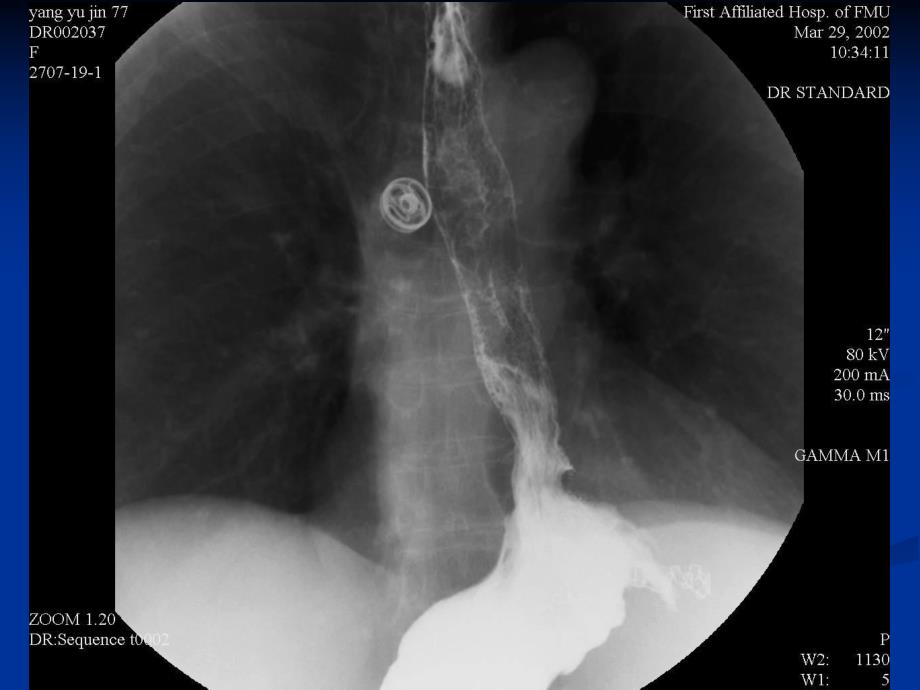

弥弥漫漫性性食食道道痉痉挛挛 轻度中度食食管管良良性性肿肿瘤瘤平平滑滑肌肌瘤瘤髓质髓质早期食道癌早期食道癌溃疡型食道癌溃疡型食道癌缩窄型食道癌缩窄型食道癌髓质型食道癌髓质型食道癌食道癌造影及食道癌造影及CT表现表现滑滑动型裂孔疝滑动型裂孔疝滑滑动动型型裂裂孔孔疝疝食食道道旁旁疝疝 食食道道异异物物挂挂钡钡征征 食道圆形金属异物食道圆形金属异物